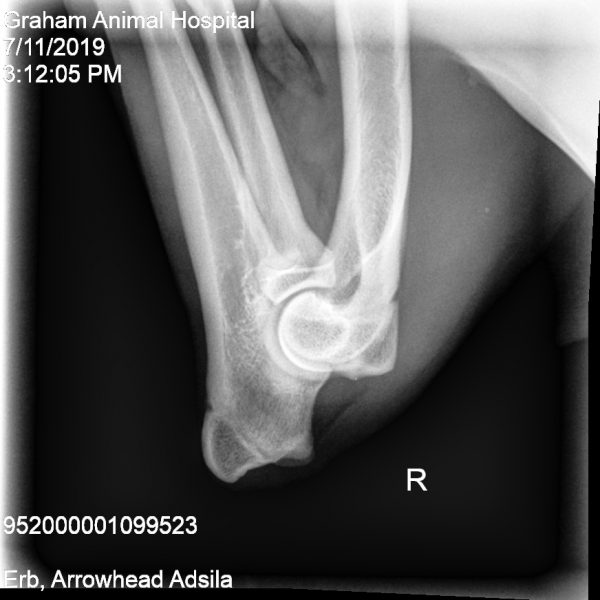

- MDBA Australian Cobberdog breeding female.

Arrowhead Adsila